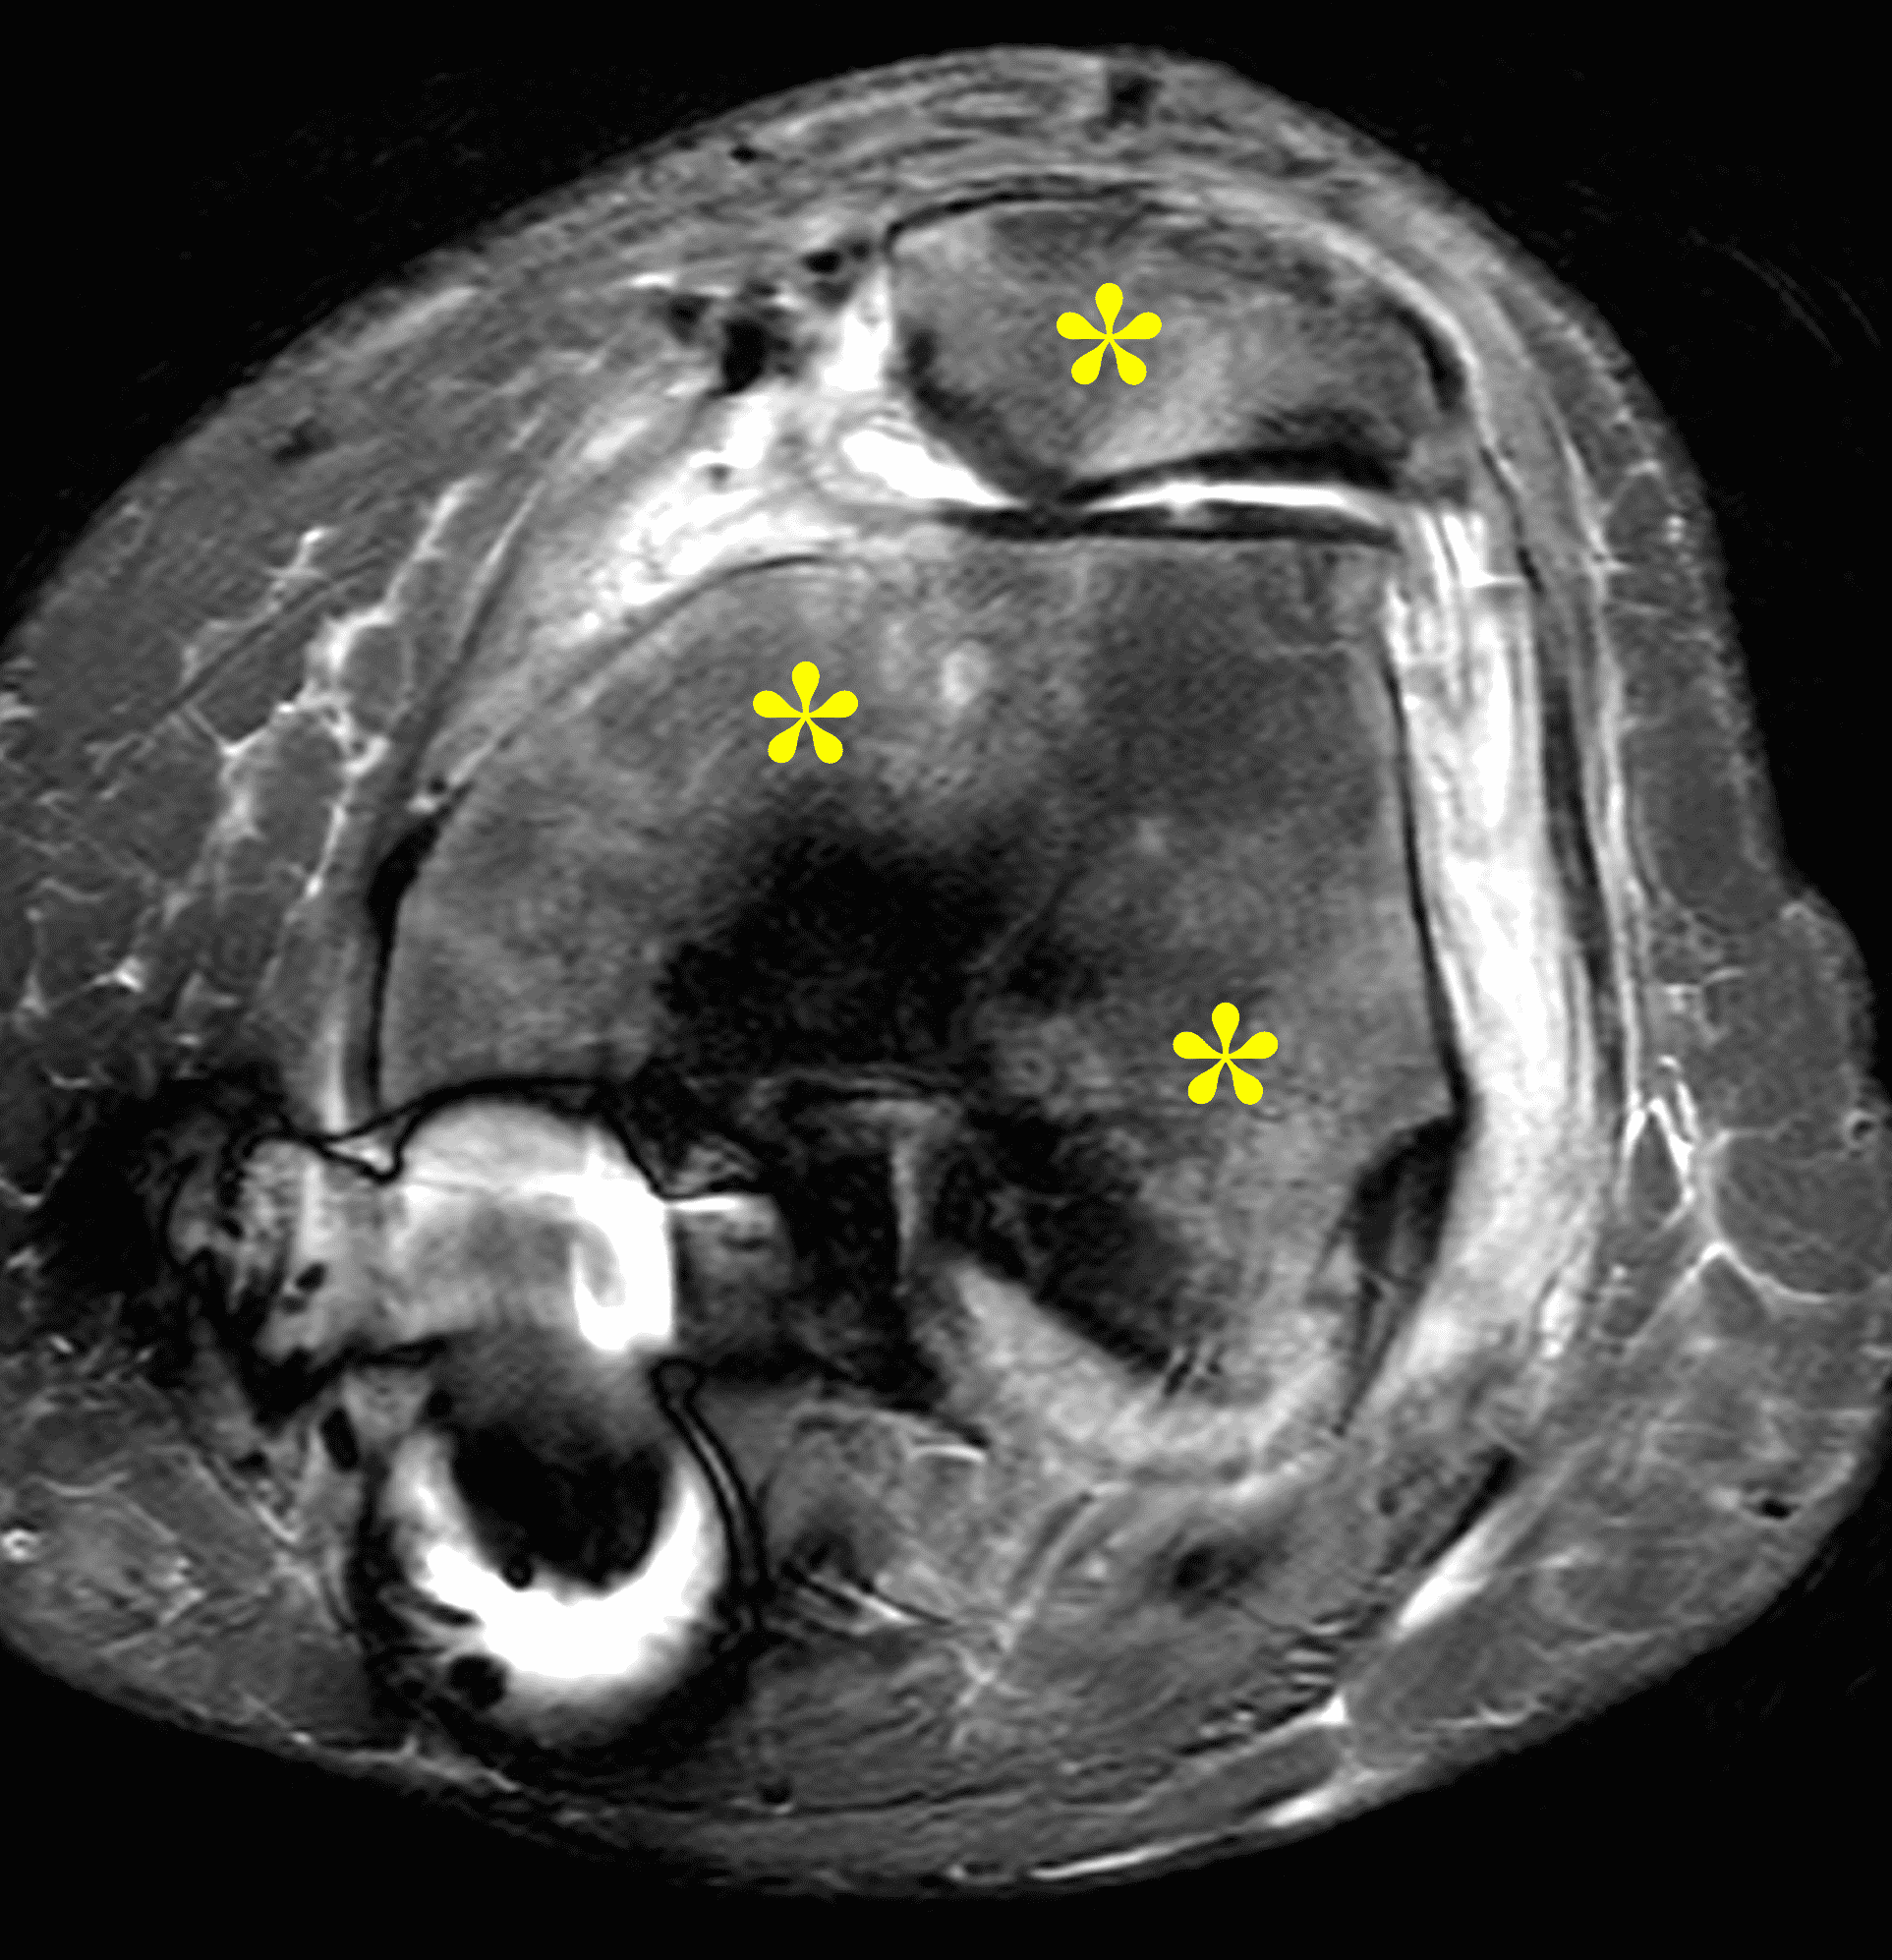

Figure 2: (2A) The coronal image shows a large effusion and severe hypertrophic synovitis (asterisks) in the knee. (2B) On the sagittal image the hypertrophic synovium (asterisks) involves the suprapatellar and infrapatellar recesses as well as the anterior and posterior intercondylar notch. A reactive lymph node (arrow) is present in the popliteal fossa. (2C) The axial image demonstrates myositis (arrows) involving the popliteus and peroneus longus muscles. Note the preserved articular cartilage, lack of erosions, and the absence of subcutaneous or marrow edema.